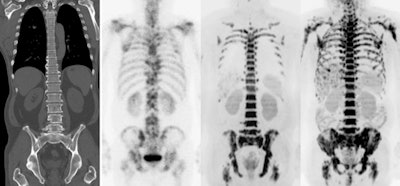

Multi-modality imaging of the skeleton shows secondary deposits in bone. Diffusion-weighted MRI (far right image) is a quantitative technique from which a biomarker called the apparent diffusion coefficient can be derived either from specifically segmented regions or from the whole skeleton. Image courtesy of Prof. Nandita deSouza.Quantitation is going to increase as artificial intelligence (AI) comes on line, and making sure it is robust and meaningful is going to be hugely important, added deSouza, who is a professor in translational imaging and co-director of the Cancer Research UK Clinical Magnetic Resonance Research Group at the Institute of Cancer Research.

Perfusion metrics have been derived with arterial spin labeling, which does not require externally administered agents. The apparent diffusion coefficient is the most widely used metric in oncology for disease detection, prognosis, and response evaluation. Postprocessing methods to derive absolute quantitation are extensively debated, but the technique is robust with good reproducibility in multicenter, multivendor trials across tumor types, according to deSouza and colleagues.